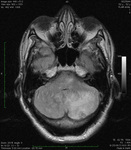

ნათხემში ვრცელი ფართობის დაზიანება წნევის ეფექტით, როგორც ჩანს მრი-ზე.

ექიმი ს.ჰ. საბრამონის კოლექციიდან; გამოყენებულია მფლობელის ნებართვით